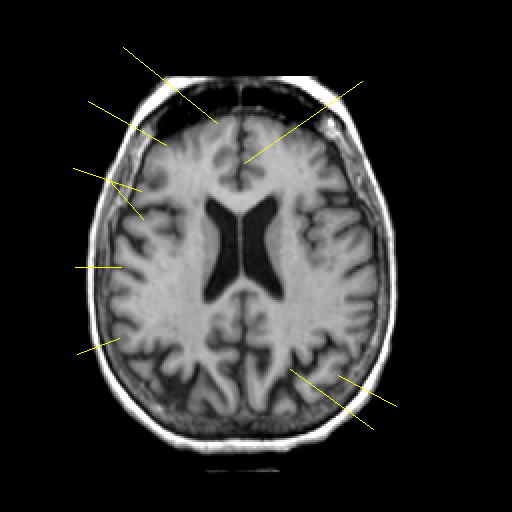

T1-weighted structural MR: Slice 33

Slice 33

Pointers

Labeled